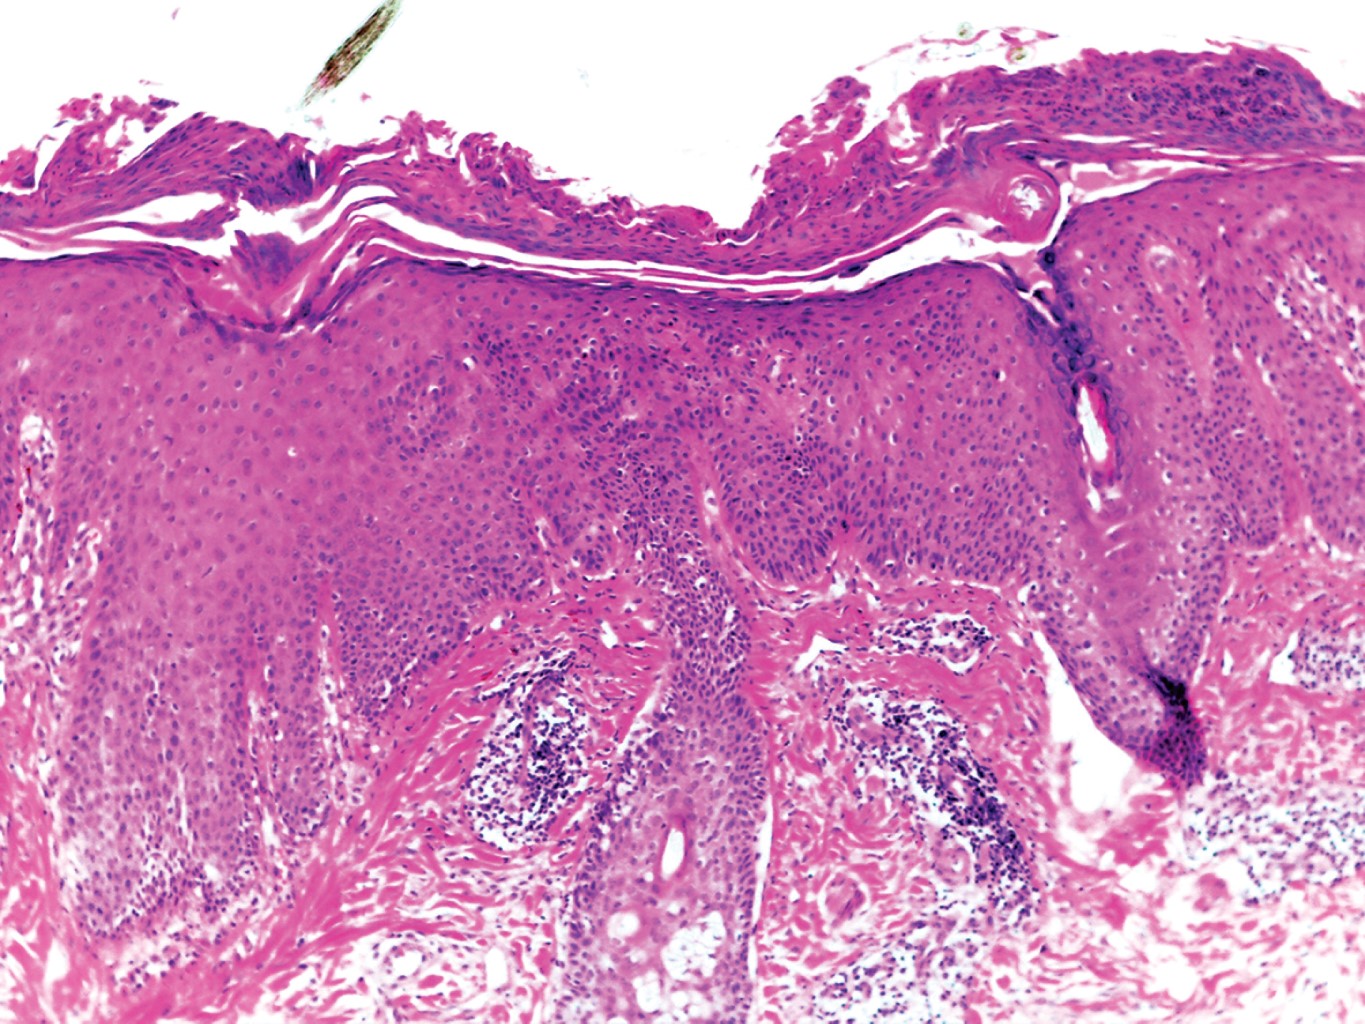

Los hallazgos histológicos son idénticos a los encontrados en el pénfigo foliáceo: ampollas subcórneas con techo ubicado en la capa granular o debajo del estrato córneo, contenido constituido por fibrina, escasos neutrófilos y algunas células acantolíticas. En lesiones tardías se observa epidermis hiperqueratósica con paraqueratosis focal y ortoqueratosis. En dermis superficial puede apreciarse discreto infiltrado inflamatorio constituido por eosinófilos y neutrófilos.

Los hallazgos del estudio histopatológico mostraron hiperqueratosis paraqueratósica, con focos de polimorfonucleares, células acantolíticas en la capa granulosa y áreas con acantosis irregular moderada. Dermis superficial y media con infiltrados moderados dispuestos en focos, constituidos principalmente por linfocitos, algunos histiocitos y escasos polimorfonucleares, los cuales rodean vasos dilatados; asimismo se observa engrosamiento de fibras de colágena (Figuras 3 y 4).